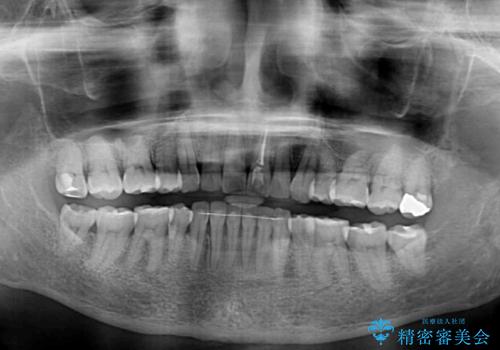

- 上下前歯を中心に、以前行った矯正治療の後戻りが気になるとのことで来院された患者様です。

後戻りは軽度であったため、インビザライン・ライトにて治療を行うこととしました。

矯正治療後は、再度後戻りすることを極力回避するために、下顎前歯の舌側を細いワイヤーを用いて保定することとしました。